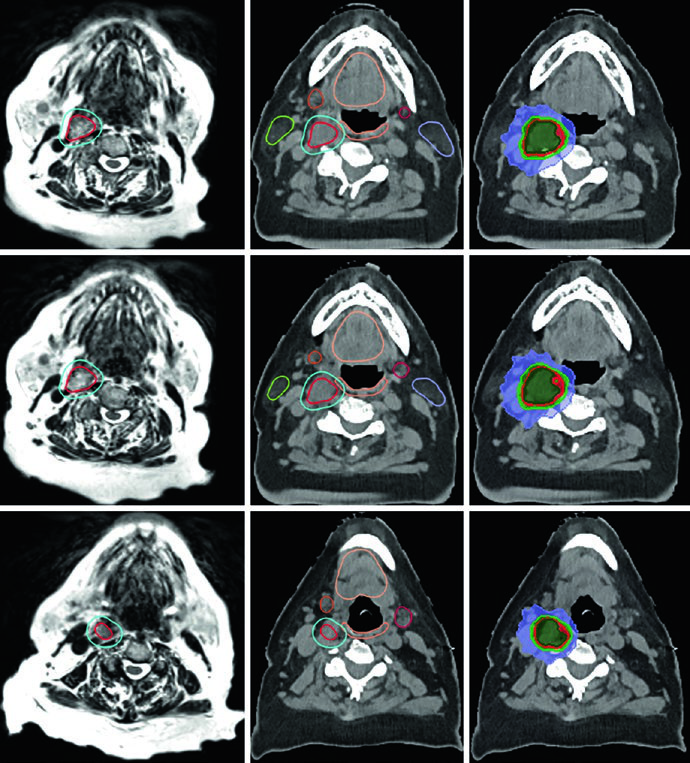

La Figura 29.14 muestra un tumor glómico carotídeo derecho que separa las arterias carótidas interna y externa. El GTV (rojo) fue delineado en RM T2 SPACE co-registrada a la TC, con expansión de 3 mm para PTV. El paciente recibió 25 Gy en 5 fracciones con líneas de isodosis de prescripción (25 Gy), 110% (27,5 Gy), 80% (20 Gy) y 50% (12,5 Gy), preservando parótidas, glándulas submandibulares, cavidad oral y pared orofaríngea.

El caso de la Figura 29.15 presenta un escenario más complejo: tumor glómico recurrente en el bulbo yugular izquierdo tras embolización y resección, tratado con 54 Gy en 30 fracciones. El GTV fue generado co-registrando imágenes de RM del diagnóstico inicial y la recurrencia, abarcando la extensión original de la enfermedad, cambios posoperatorios, lecho tumoral y enfermedad recurrente con cobertura hasta la base del cráneo. Un margen de 0,3 cm definió el PTV. Múltiples OARs — tronco encefálico, mandíbula, parótidas bilaterales, médula con PRV, pared orofaríngea, cavidad oral y labios — fueron meticulosamente delineados.